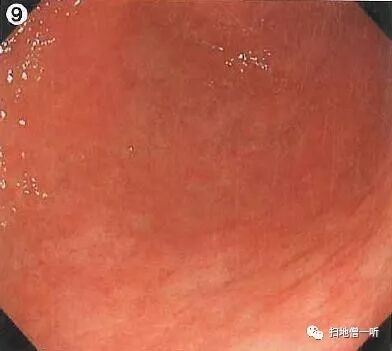

背景粘膜光滑而有光泽,呈现均一的橘红色粘膜像,胃底腺区域RAC阳性,存在胃底腺息肉,以上均提示HP未感染。幽门前区大弯侧可见单发糜烂伴血痂附着,此病变为重点观察处。HP阴性的幽门前区经常会见到此类多发糜烂灶,故与癌的鉴别非常困难,鉴于此病例糜烂为单发,故需要进一步观察。